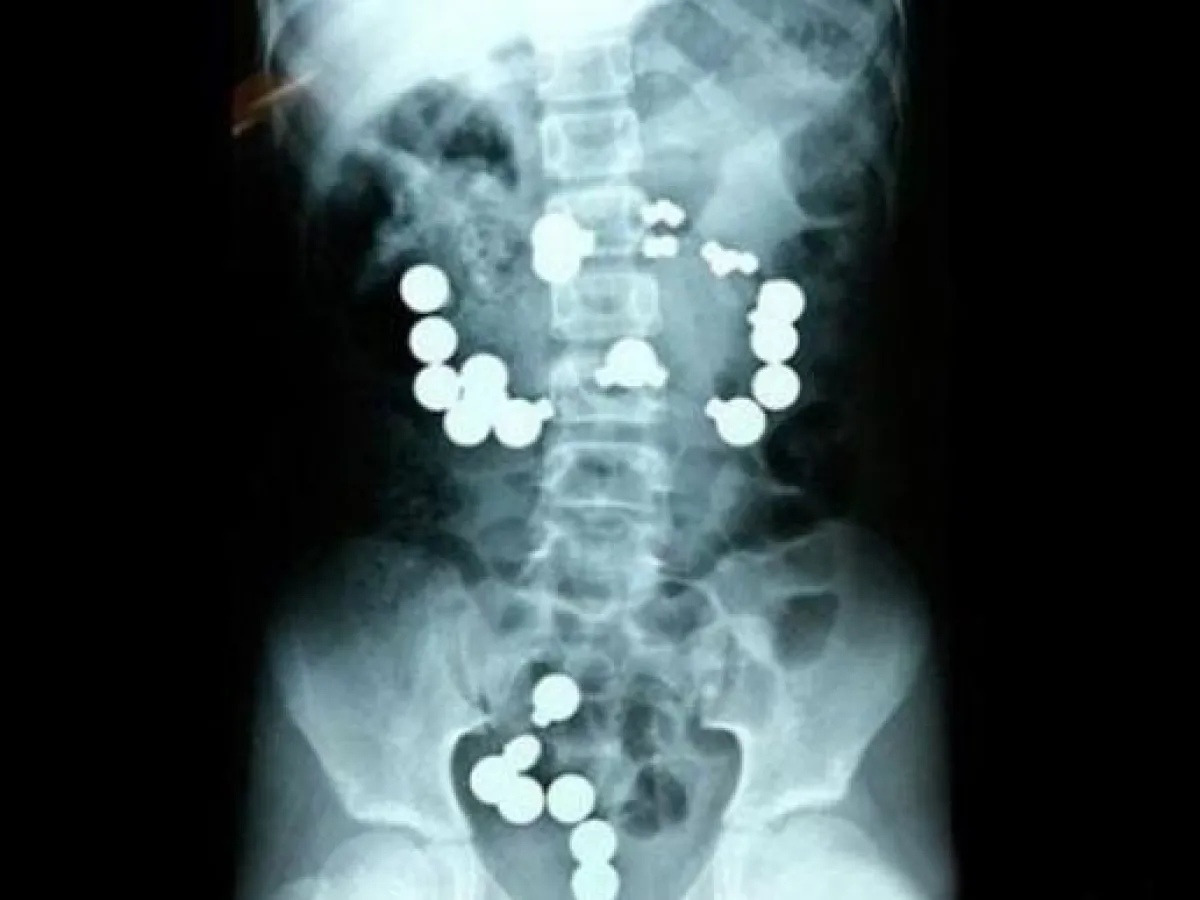

وقد أظهرت الآشعة فوق الصوتية وجود القطع المعدنية بالجهاز الهضمي للطفل ، وهو ما استلزم إجراء عملية جراحية لاستخراجهم ، وهو الآن في حالة مستقرة غير أن الأم تواجة احتمالات التغريم من قبل السلطات بسبب اهمالعا طفلها.